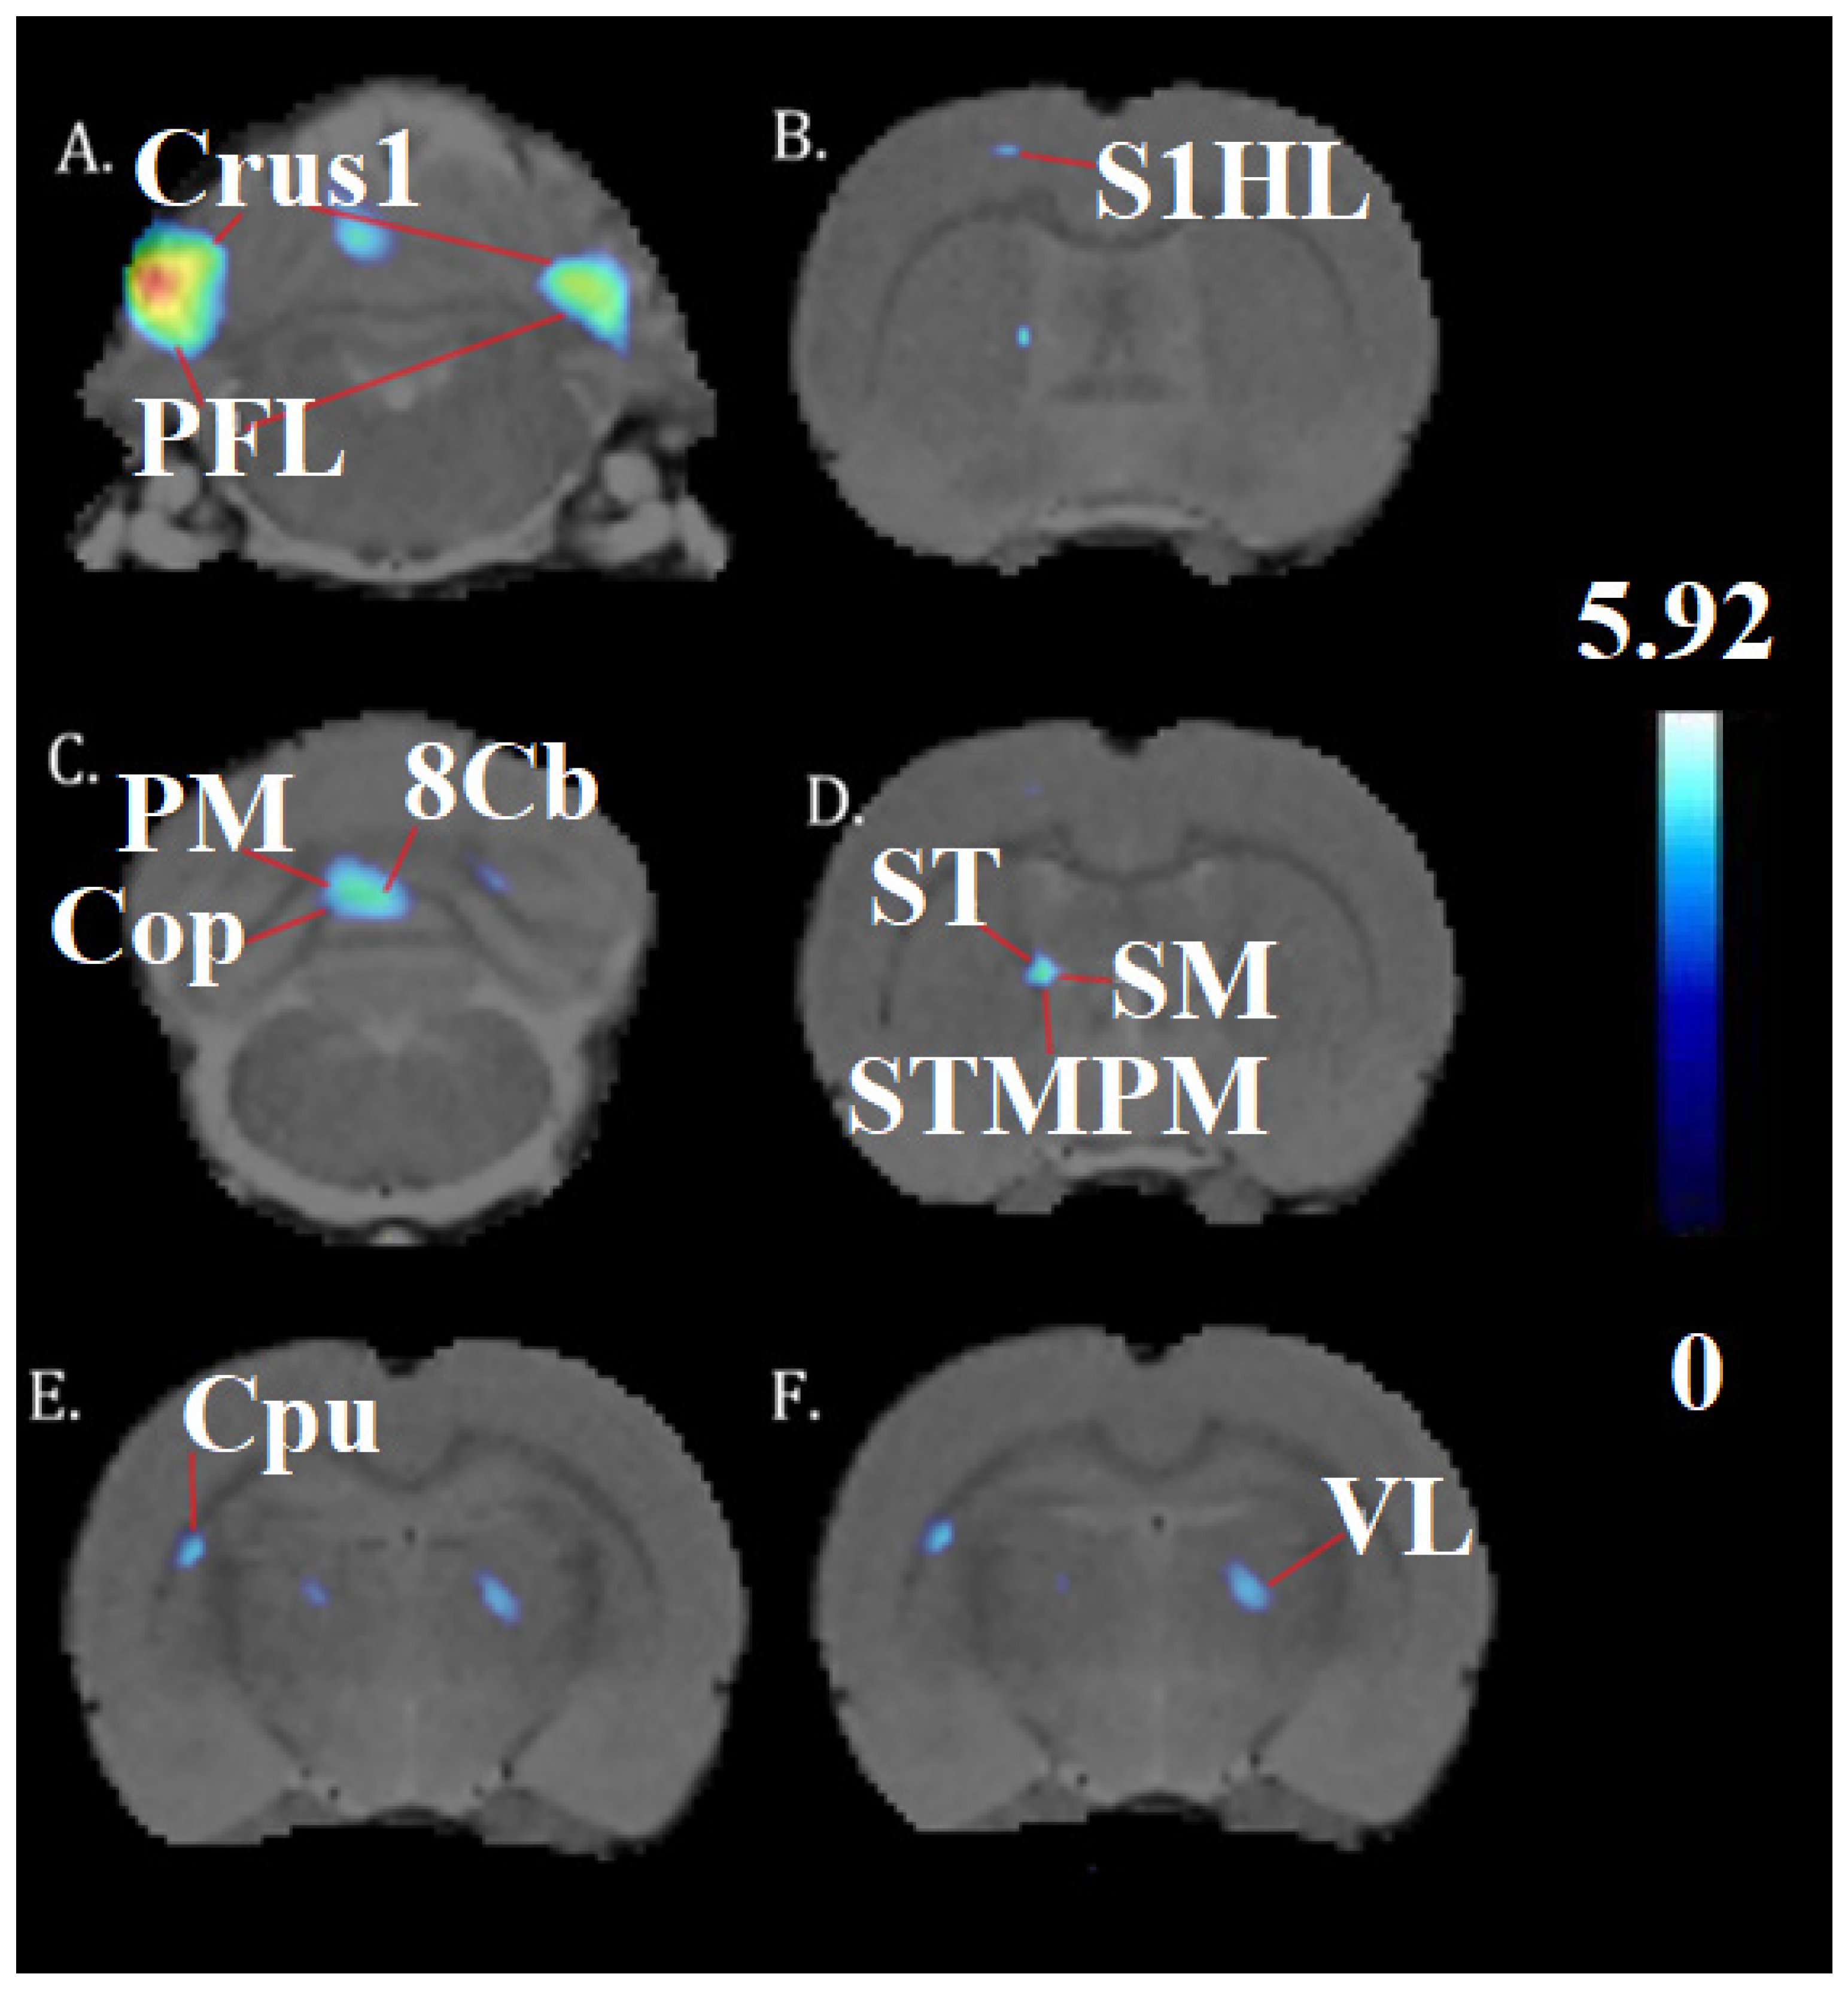

| Brain Region | General Cluster Location | Medial–Lateral (mm) | Dorsal–Ventral (mm) | Anterior–Posterior (mm) | t-Value | z-Score | KE |

|---|---|---|---|---|---|---|---|

| Crus1, PFL | Cerebellum | −5.0 | 6.0 | −11.4 | 5.92 | 4.45 | 2496 |

| PFI, Crus1 | Cerebellum | 4.0 | 5.2 | −11.0 | 6.18 | 4.57 | 2175 |

| 8cb, PM, Cop | Cerebellum | −0.8 | 4.4 | −12.4 | 5.00 | 3.98 | 2103 |

| St, sm, stmpm | Stria terminalis, thalamus | −1.8 | 5.8 | −0.8 | 4.92 | 3.94 | 238 |

| CPu | midbrain | −4.4 | 4.6 | −2.4 | 4.68 | 3.80 | 193 |

| VL | Thalamus | 1.8 | 5.6 | −2.4 | 4.44 | 3.66 | 174 |

| S1HL | Somatosensory cortex | −2.2 | 1.8 | −0.4 | 4.06 | 3.42 | 58 |